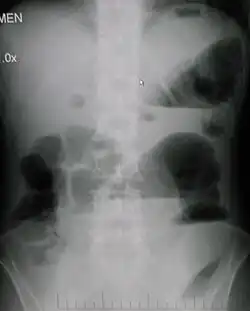

| Upright abdominal X-ray demonstrating a small bowel obstruction. Note multiple air fluid levels. | |

Causes of bowel obstruction include adhesions, hernias, volvulus, endometriosis, inflammatory bowel disease, appendicitis, tumors, diverticulitis, ischemic bowel, tuberculosis and intussusception.[1][2] Small bowel obstructions are most often due to adhesions and hernias while large bowel obstructions are most often due to tumors and volvulus.[1][2] The diagnosis may be made on plain X-rays; however, CT scan is more accurate.[1] Ultrasound or MRI may help in the diagnosis of children or pregnant women.[1]

Radiological signs of bowel obstruction include bowel distension (small bowel loops dilated >3 cm) and the presence of multiple (more than 2) air-fluid levels on supine and erect abdominal radiographs.[16] Ultrasounds may be as useful as CT scanning to make the diagnosis.[17]